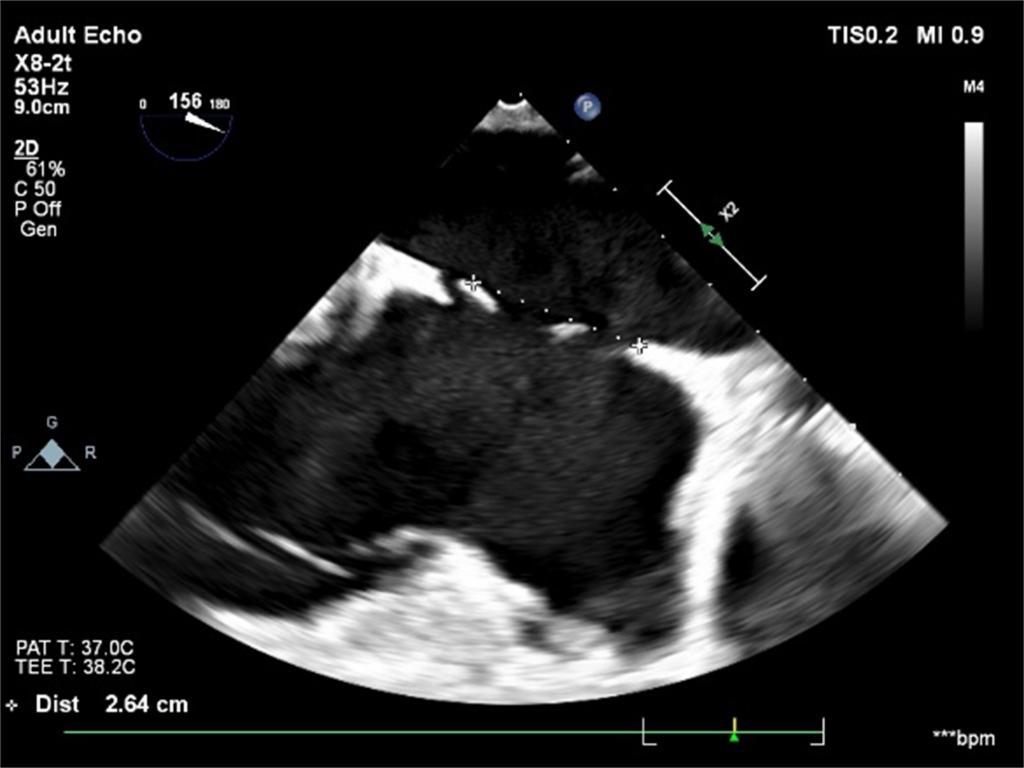

根据手术路径,在全身麻醉后,麻醉医生放置食道超声探头,进行仔细检查,发现患者的房间隔缺损实际有3个。侯江龙教授通过经胸小切口在非体外循环下尝试将较大的两个小缺损融合成一个,然后再用稍大的封堵伞挤压最小的缺损。最终,在术中经食管超声的实时引导下,房间隔缺损封堵术顺利完成,术后几乎无残余分流,避免了开胸和体外循环手术带来的巨大创伤,为患者快速康复提供了坚实的基础。患者术后恢复良好,第二天顺利出院。